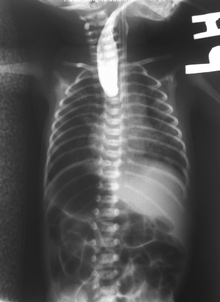

If any of the above signs/symptoms are noticed, a catheter is gently passed into the esophagus to check for resistance. If resistance is noted, other studies will be done to confirm the diagnosis. A catheter can be inserted and will show up as white on a regular x-ray film to demonstrate the blind pouch ending. Sometimes a small amount of barium (chalk-like liquid) is placed through the mouth to diagnose the problems.